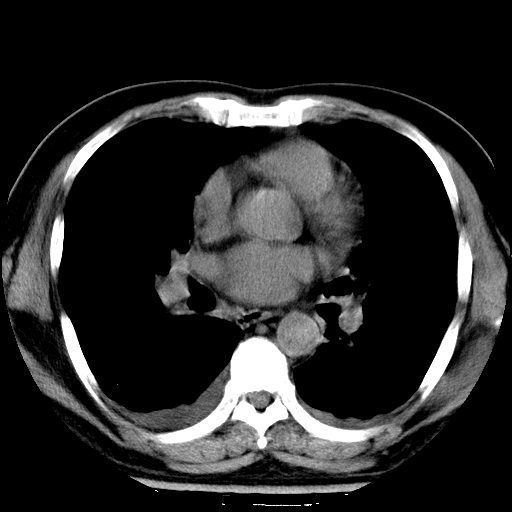

男,65岁,咳嗽、咳痰、发热5天。

慢支 肺间质纤维化合并感染!

支气管扩张合并感染,胸膜肥厚

考虑慢支并感染,肺间质纤维化。

两肺间质性炎症并感染

慢支,肺心病

支持慢性支气管炎伴感染,双侧少量胸腔积液.

两肺间质纤维化,支扩合并感染,双侧胸腔积液

感染,肺间质纤维化。

慢支 肺间质纤维化合并感染

支持慢性支气管、肺间质纤维化合并感染。

慢性支气管炎并感染,支扩,双侧少量胸腔积液.